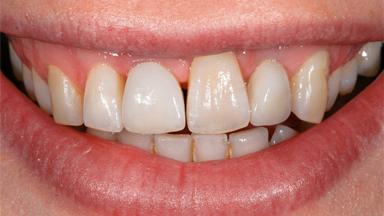

A male patient had lost teeth 11 and 22 as a result of a bicycle accident at age 14. In his adolescent years, a removable prosthesis had replaced the missing teeth. At age 21, the patient was referred by his dentist to the university clinic for treatment of the missing teeth 11 and 22 with implants. He was in good health and a nonsmoker. The absence of teeth 11 and 22 over many years had led to significant atrophy of the alveolar ridge, particularly at site 11. As a first step, the alveolar ridge was augmented using a block graft to replace the lost bone. A Straumann SP implant (diameter 4.1 mm, length 12 mm; Institut Straumann AG, Basel, Switzerland) and a Straumann Narrow Neck implant (length 10 mm) were inserted in the correct location and axial position at sites 11 and 22, respectively, six months later. After three months of healing and subsequent reentry, the patient returned to the referring dentist to receive the prosthetic restoration. The patient was seen again six months after the restoration had been placed. The frontal view showed a high smile line, an irregular gingival profile, and a bluish-gray tinge to implant crowns 11 and 22 compared to the natural dentition.